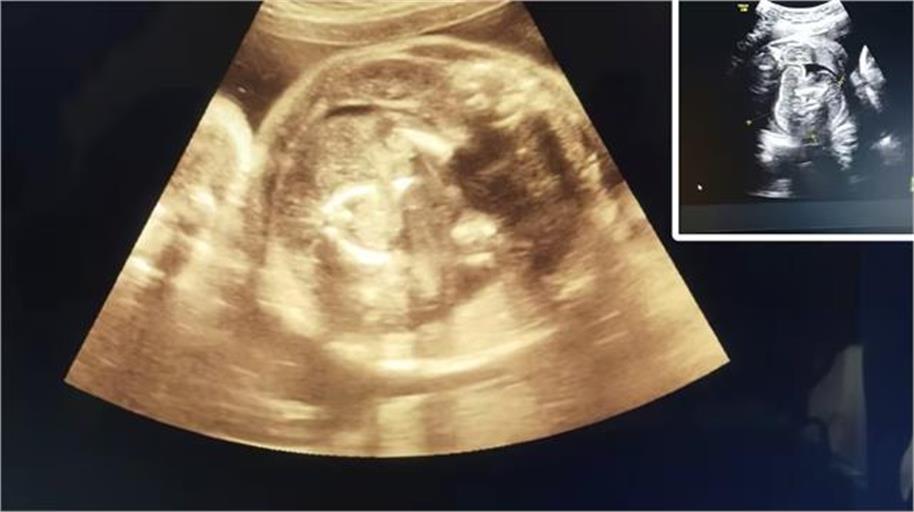

महाराष्ट्र के बुलढाना जिले के एक सरकारी अस्पताल में एक दुर्लभ चिकित्सा मामला सामने आया, जिसने डॉक्टरों को भी हैरान कर दिया। जिले के मोताला तहसील से आई 32 वर्षीय गर्भवती महिला की सोनोग्राफी के दौरान डॉक्टरों ने पाया कि उसके गर्भ में पल रहे बच्चे के पेट में भी एक भ्रूण मौजूद है।

डॉक्टर प्रसाद अग्रवाल ने सोनोग्राफी करते समय इस असामान्य स्थिति को देखा, जिसके बाद उन्होंने दोबारा जांच की और अपने वरिष्ठ डॉक्टरों को जानकारी दी। महिला को किसी भी प्रकार की जटिलता से बचाने के लिए तुरंत संभाजीनगर रेफर कर दिया गया।

इस स्थिति को चिकित्सा जगत में Fetus in Feto कहा जाता है, जो बेहद दुर्लभ मामला है। सिविल सर्जन डॉ. भागवत भुसारी के अनुसार, दुनियाभर में अब तक ऐसे लगभग 200 मामले सामने आ चुके हैं, जिनमें से भारत में केवल 15 से 20 ही दर्ज हुए हैं। विशेषज्ञों का कहना है कि मां को कोई खतरा नहीं होगा, लेकिन नवजात के लिए जल्द से जल्द उपचार आवश्यक होगा ताकि उसकी सामान्य वृद्धि प्रभावित न हो।